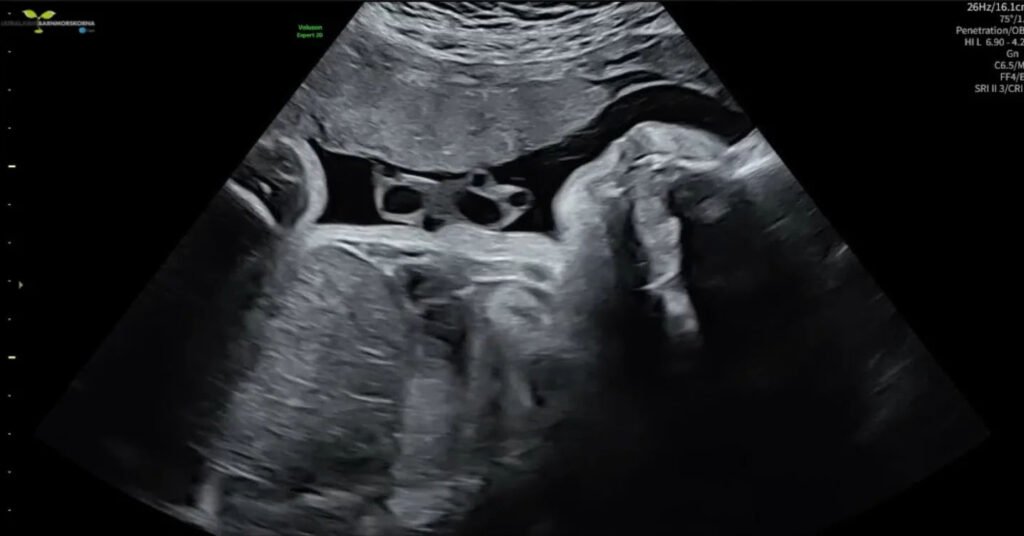

She took a test. By Wednesday she was sitting in an ultrasound appointment being told she was between 28 and 30 weeks pregnant.

The ultrasound on Wednesday confirmed the baby is healthy despite the unmonitored first seven months.

“It’s a very healthy little one,” Ferm said. “I was scared beforehand because I’ve been living life as usual. But everything looked great with the baby.”